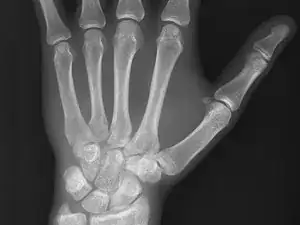

Medical imaging is the process of creating visual representations of the internal structures of the body beneath the skin and bones. These images can then be used for clinical analysis, diagnosis and discovery of abnormalities, and to create plans for medical intervention. Medical imaging uses a variety of technologies based on the area of analysis, including but not limited to “X-ray radiography, magnetic resonance imaging, ultrasound, endoscopy, elastography, tactile imaging, thermography, medical photography, and nuclear medicine functional imaging techniques as positron emission tomography (PET) and single-photon emission computed tomography (SPECT).” (Wikipedia)